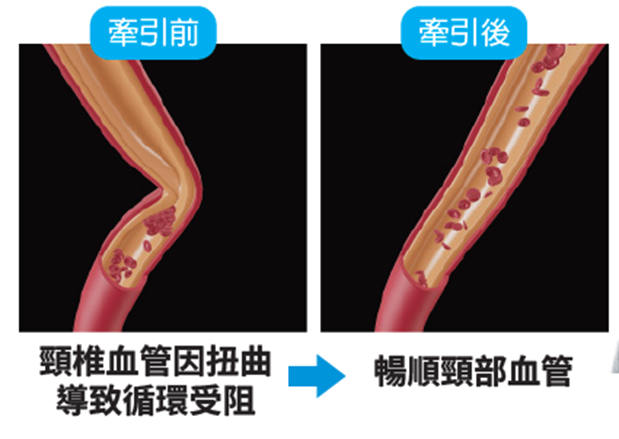

(3)頸椎內外血管扭曲:

抬頭、擺動頭頸部或長期姿勢不良等,導致頸椎內外血管流動不暢順,影響血液來往腦區域,導致頭暈、頭痛。

目前,採用強力後枕牽引器(N05b) 拉直頸椎,減少病變對神經的受壓,減少刺激交感神經,同時可拉直血管,使血液流通暢順。此方法可從根源解決頸源性頭暈、頭痛、眼花等問題,非常有效。

先讓病人頭部保持後仰姿勢,並以後枕作為支點,再扭動兩側升降桿的扭制,產生巨大後枕牽引力(最高可達到20Kg)有效拉直上頸部,減少刺激交感神經,減少頸椎神經受壓和暢順頸部血管。